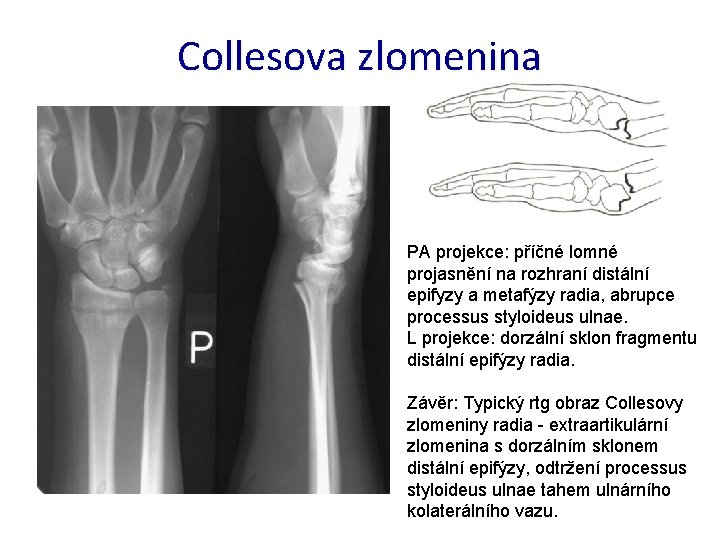

Collesova zlomenina PA projekce: příčné lomné projasnění na rozhraní distální epifyzy a metafýzy radia, abrupce processus styloideus ulnae. L projekce: dorzální sklon fragmentu distální epifýzy radia. Závěr: Typický rtg obraz Collesovy zlomeniny radia - extraartikulární zlomenina s dorzálním sklonem distální epifýzy, odtržení processus styloideus ulnae tahem ulnárního kolaterálního vazu.